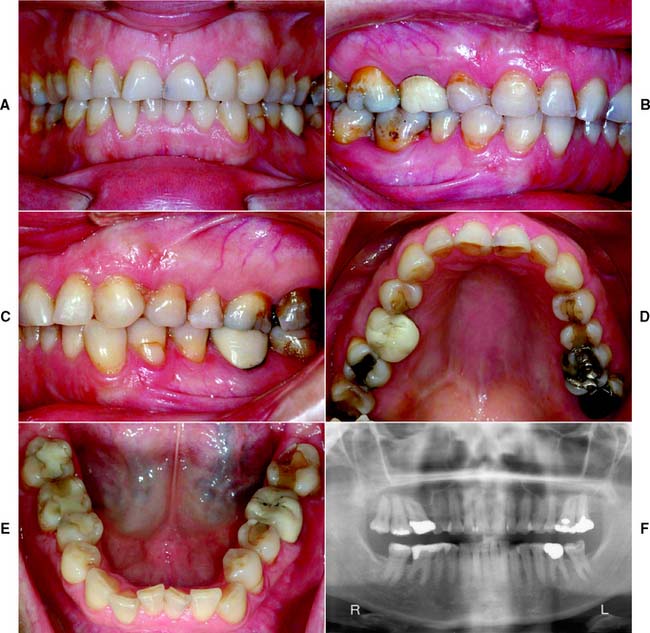

This class (Figs. 1-31 and 1-32) is characterized by substantially compromised location and extent of edentulous areas in both arches, abutment condition necessitating substantial localized adjunctive therapy, occlusal characteristics necessitating reestablishment of the entire occlusion without a change in the occlusal vertical dimension, and residual ridge conditions.

Fig. 1-31 Class III patient. This patient is categorized as Class III because the edentulous areas are located in both arches and there are multiple such locations within each arch. The abutment condition is substantially compromised as a result of the need for extracoronal restorations. There are teeth that are extruded and malpositioned. The occlusion is substantially compromised because reestablishment of the occlusal scheme is required without a change in the occlusal vertical dimension. A, Frontal view, maximum intercuspation. B, Right lateral view, maximum intercuspation. C, Left lateral view, maximum intercuspation. D, Occlusal view, maxillary arch. E, Occlusal view, mandibular arch. F, Frontal view, protrusive relationship. G, Right lateral view, right working movement. H, Left lateral view, left working movement. I, Full-mouth radiographic series.

(From McGarry TJ, et al: Classification system for partial edentulism. J Prosthodont 11:181, 2002.)